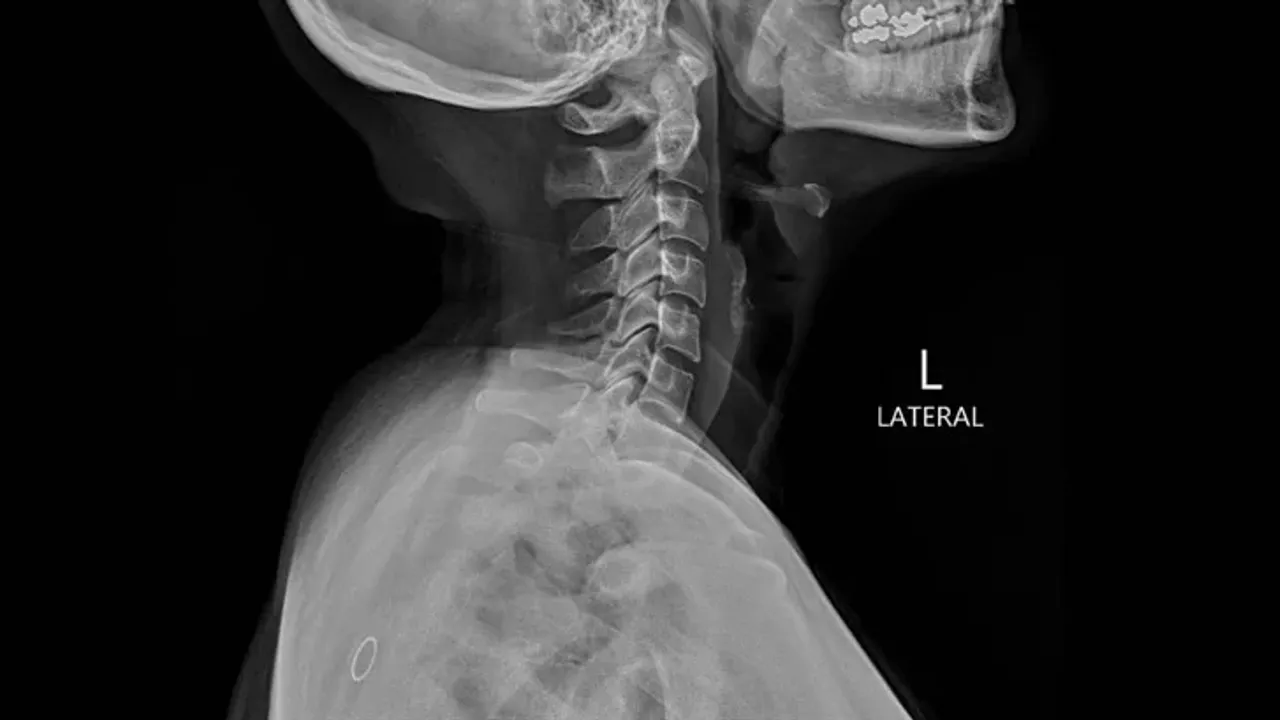

Yapay zeka, tıp dünyasında hayat kurtarmak yerine bu kez manipülasyon aracı olarak karşımıza çıkıyor. Araştırmalar, deepfake teknolojisiyle oluşturulan sahte tıbbi görüntülerin, radyologların büyük çoğunluğunu yanlış teşhis koymaya itecek kadar kusursuz olduğunu gösteriyor. Bu durum, sağlık sisteminin dijital güvenilirliğini doğrudan tehdit ediyor.

Sahte görüntüler sadece teşhis hatalarına değil, aynı zamanda milyonlarca liralık sigorta dolandırıcılığına da kapı aralıyor. Kötü niyetli aktörler, sağlıklı bir hastanın MR sonuçlarına yapay zeka ile hastalık verileri ekleyerek haksız kazanç elde edebiliyor. Bilim insanları, bu manipülasyonları tespit etmek için dijital "su damgası" ve blockchain tabanlı doğrulama sistemleri üzerinde çalışıyor.

Hastanelerin sadece fiziksel değil, dijital altyapılarını da koruma altına alması artık bir zorunluluk. Uzmanlar, görüntüleme cihazlarının ağ bağlantılarının uçtan uca şifrelenmesi ve her görüntünün dijital bir imzaya sahip olması gerektiğini vurguluyor. Gelecekte, bir röntgenin gerçekliğini kanıtlamak, onu yorumlamak kadar kritik hale gelecek.